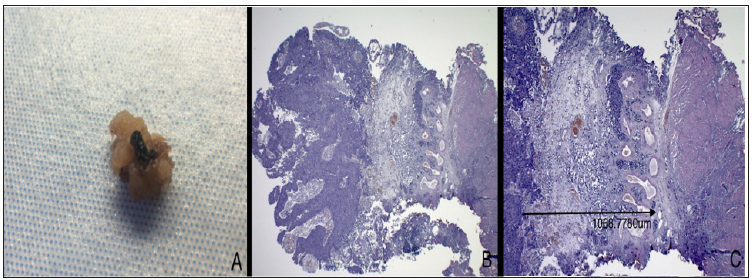

Endoscopic specimen, formalin fixed in 10% buffered formalin solution and unmanipulated for optimum anatomic orientation is sent to pathology lab. Adequate dissection of the gross specimen is essential for accurate measurements: the resected neoplasm is transverse sectioned and whole included in paraffin block and evaluated on ematossiline-eosine section. All slides are digitally acquired using Leica Aperio Scan scope and measured via Aperio Image scope digital slide viewer. Tumor depth is accurately evaluated by examining the deepest infiltration measuring the depth to which tumor cells have invaded submucosa (in mm), starting from the membrane basalis at a right angle, down to the deepest point of invasion (Figure 1).

Figure 1: In A. Gross evaluation of a resected specimen, in this case a polypoid lesion, with easily identifying stalk; the deep surgical line of excision is stained with India Ink for margin status assessment purpose. B. Ematossiline-eosine section at 2,5x magnification, showing a perfectly oriented specimen, with loyal representation and clear low-power identification of lamina propria structures. C. Same slides, 4x magnification, the arrow indicate the measurement of depth of invasion identified as the deepest tumor cell in a perpendicular line to the membrane basalis.